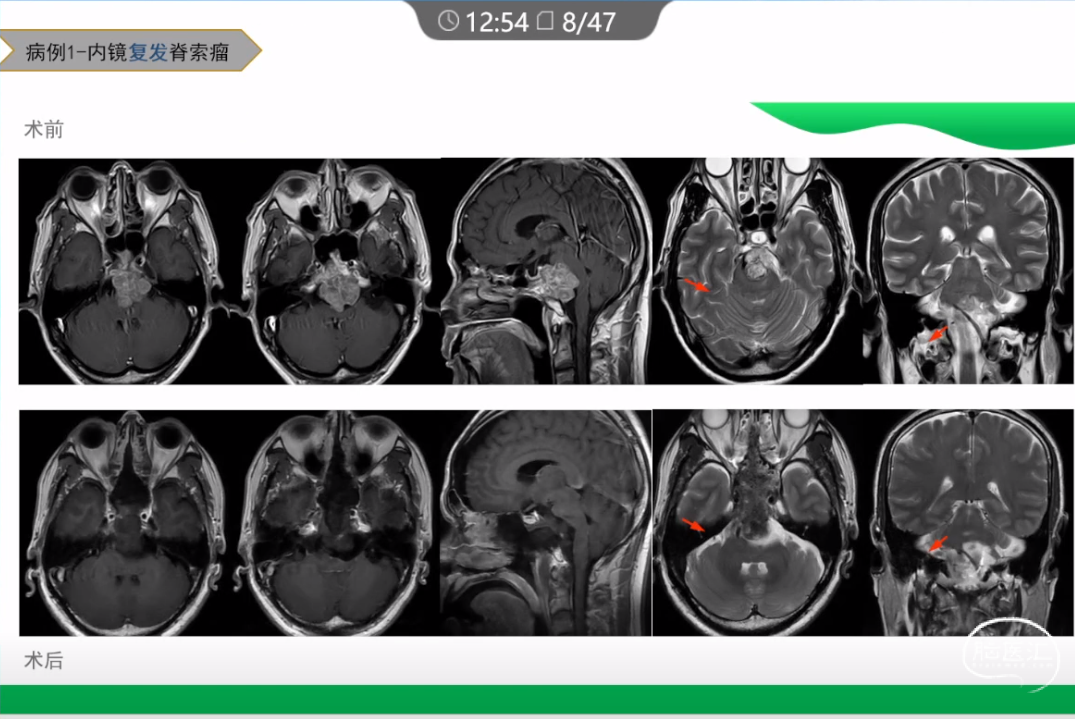

本文主要内容为:脊索瘤临床特点、治疗选择,以及多个手术病例。